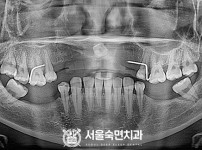

상악동거상술, 뼈이식 / 숙면임플란트 11개 - 포인트임플란트 (이*정님)

해당 게시물은 의료법 제56조에 의거하여 로그인 후 열람이 가능합니다.

구분 임플란트